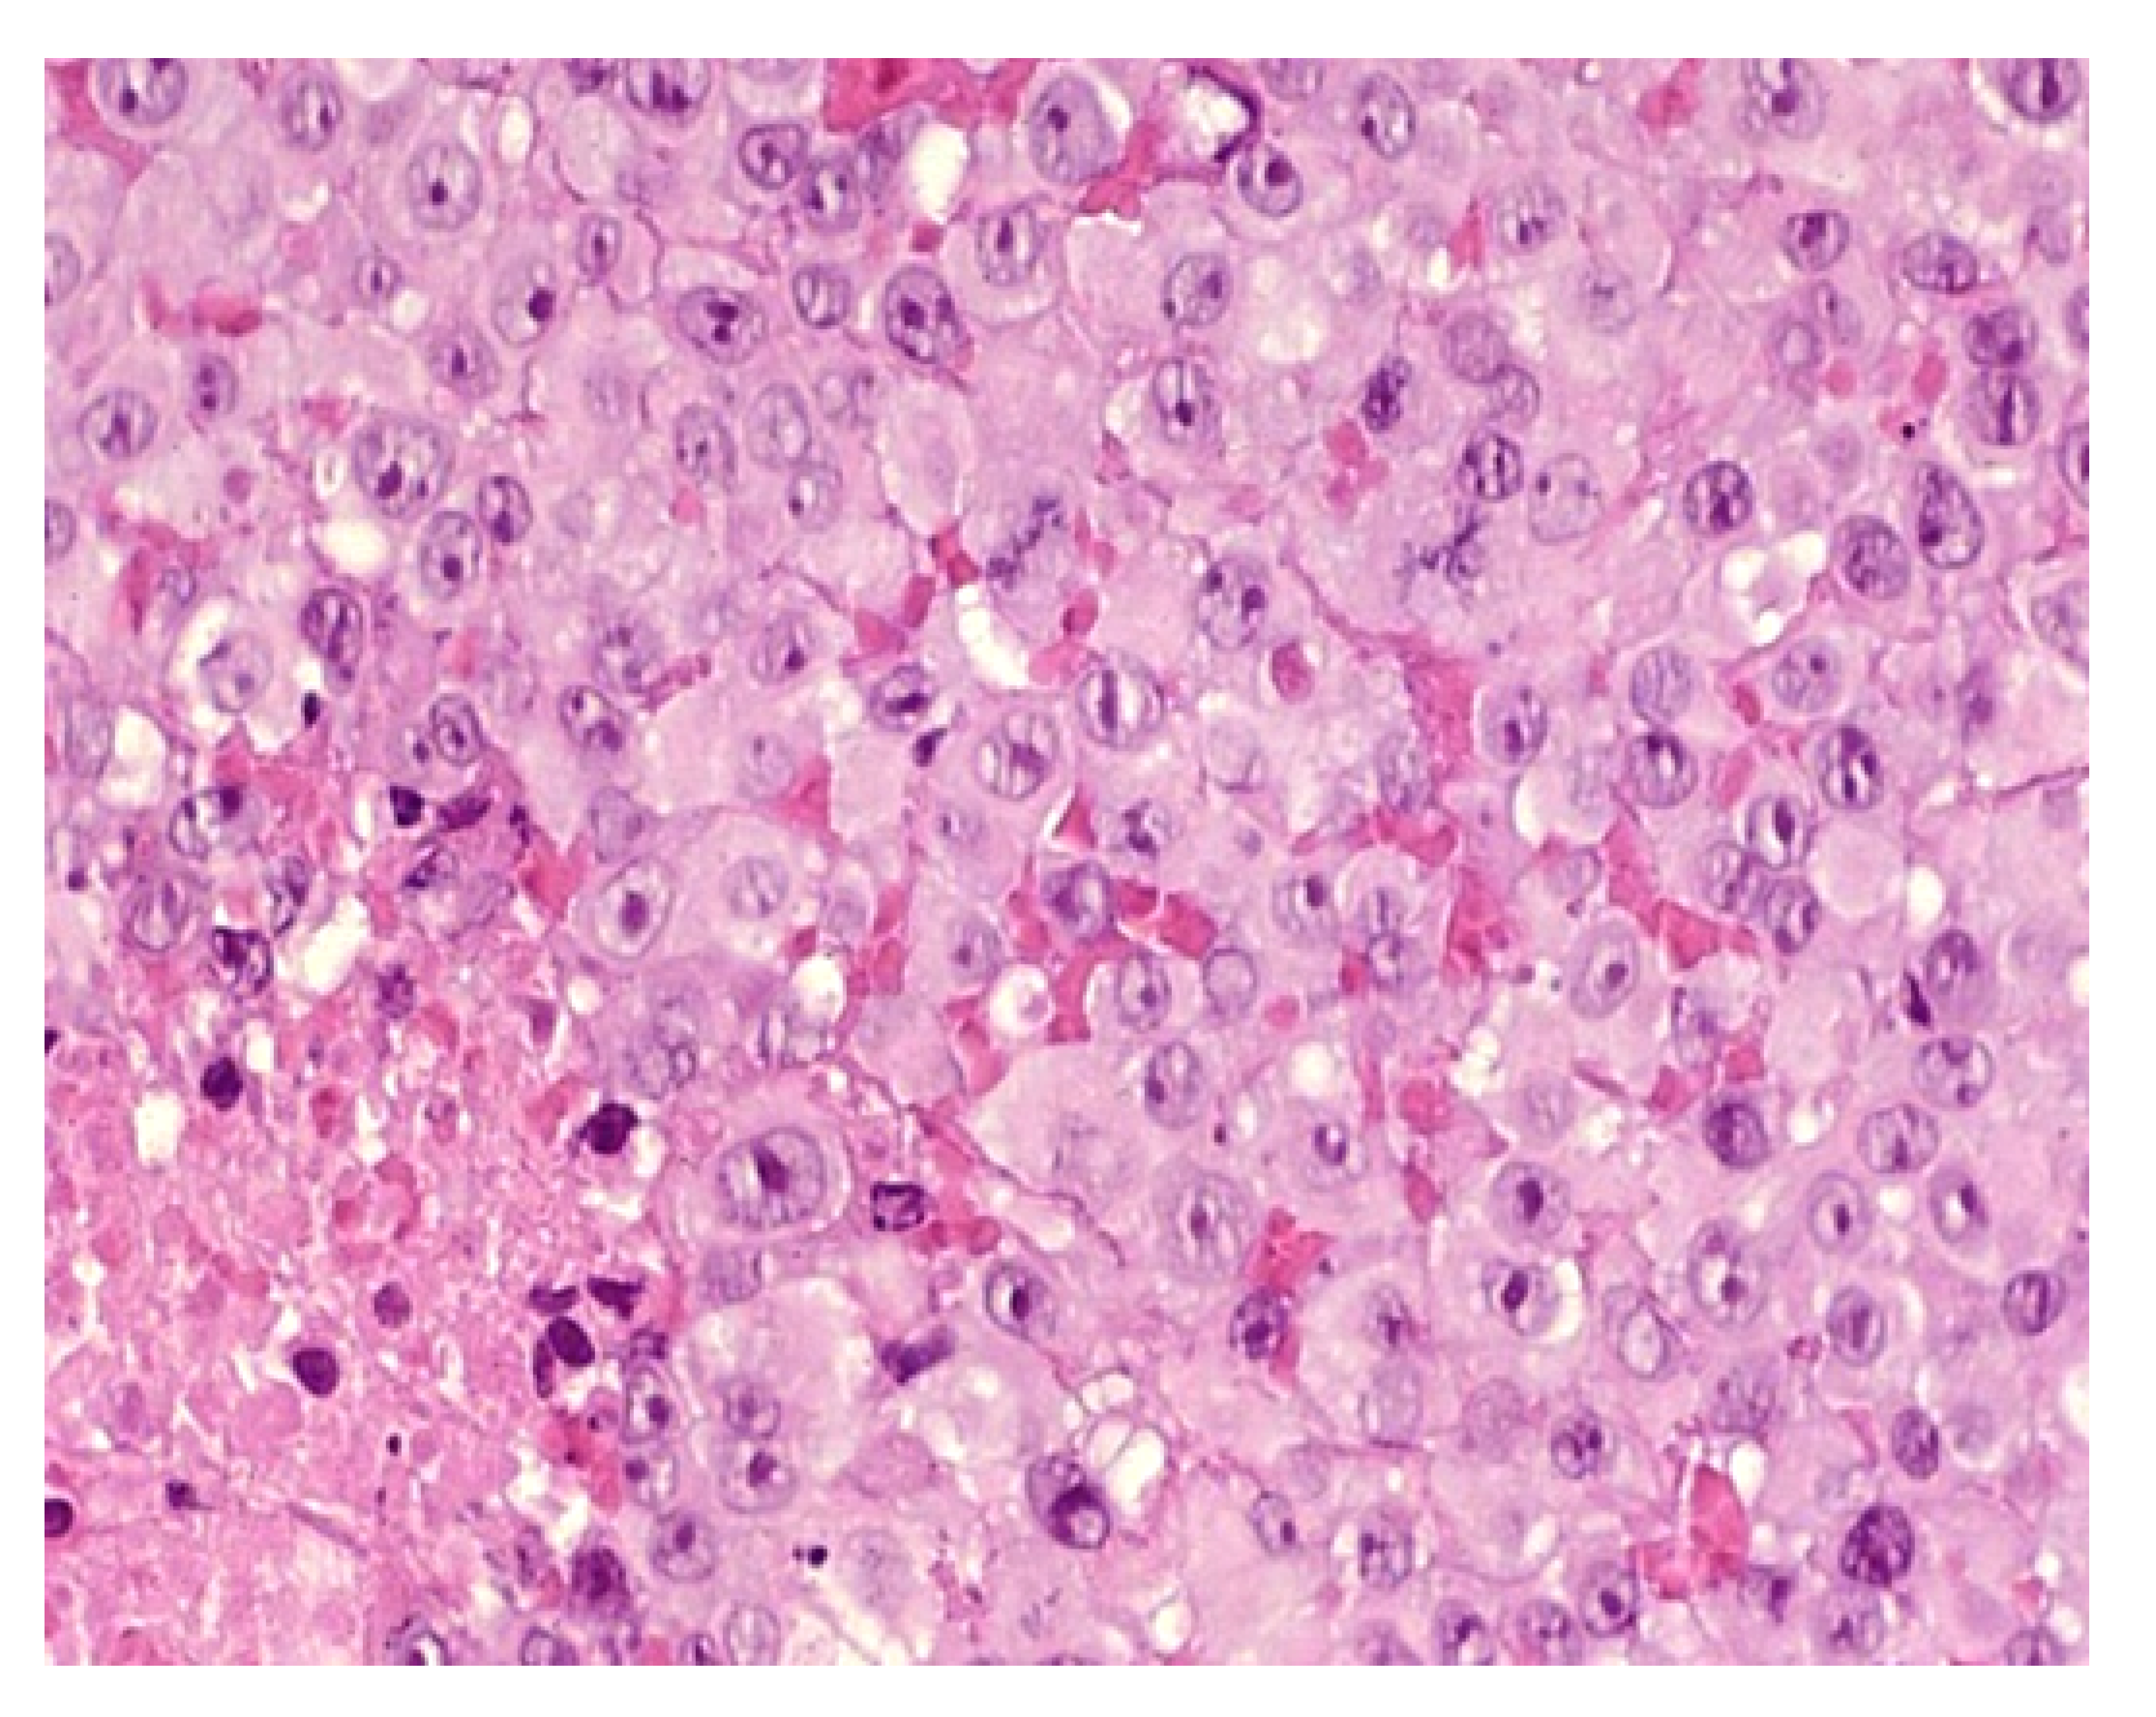

Histology

Classically, MRT is described as sheets of polygonal cells with abundant acidophilic cytoplasm, eccentric round vesicular nuclei, prominent nucleoli, and periodic acid Schiff-positive hyaline cytoplasmic inclusions (Figure 6). Loss of immunoreactivity for INI1 is a distinguishing (but not pathognomonic) feature of MRT. The disorder is associated with loss of the tumor suppressor SMARCB1/INI1/SNF5/BAF47 on chromosome 22q11 due to either heterozygous germline deletions or somatic mutations.

Figure 6.

40× Rhaboid tumor. Very atypical large cells.